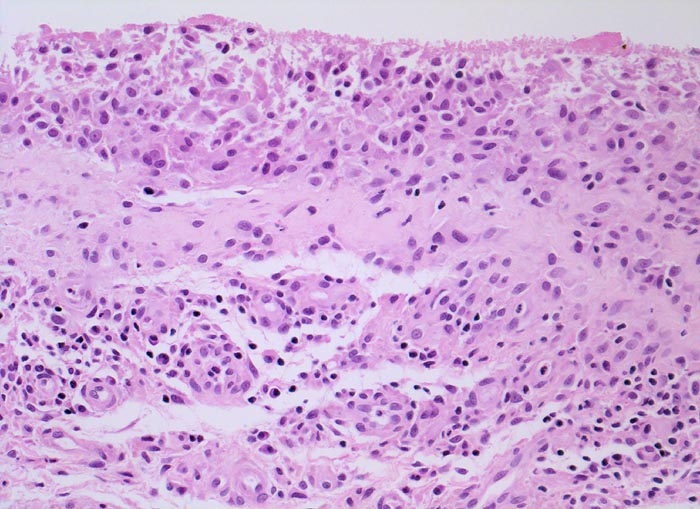

Typische histologische Veränderungen sind eine synoviale Zottenhyperplasie, Verbreiterung der Deckzellschicht unter Einschluss mehrkerniger Riesenzellen, Fibrinexsudate und synoviale Ulzerationen, Infiltrate von Lymphozyten teils in Form von Lymphfollikeln, Plasmazellen, neutrophilen Granulozyten, Makrophagen und Siderophagen, sowie Einschlüsse von Knorpel- und Knochenfragmenten (Detritussynovialitis). Die histologischen Befunde der Synovialis korrelieren oft nicht mit den klinischen Angaben. Trotz fortgeschrittener Gelenkdestruktion mit ausgeprägter klinischer Symptomatik können Synovialektomiepräparate nur sehr geringe pathologische Veränderungen zeigen. Oft ist auch nicht mehr zu eruieren, welche Läsionen Folge der Grundkrankheit und welche Folge diverser intraartikulärer Therapien oder begleitender Superinfektionen sind.

• Stark proliferierte mehrreihige synoviale Deckzellschicht.

• Herdförmig Fibrinauflagerungen durchsetzt von neutrophilen Granulozyten.

• Hyperzelluläres Stroma mit lymphoplasmazellulärem Entzündungsinfiltrat mit Ausbildung von Lymphfollikeln.